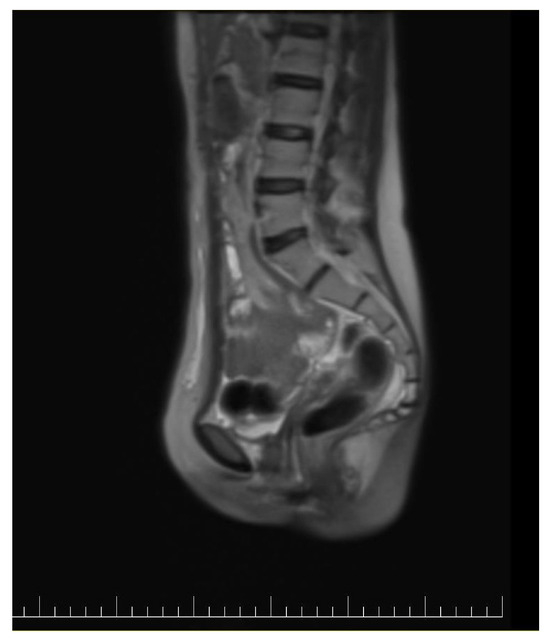

Figure 2.

Preoperatory sagittal view of a CT image presenting a giant ovarian mass.